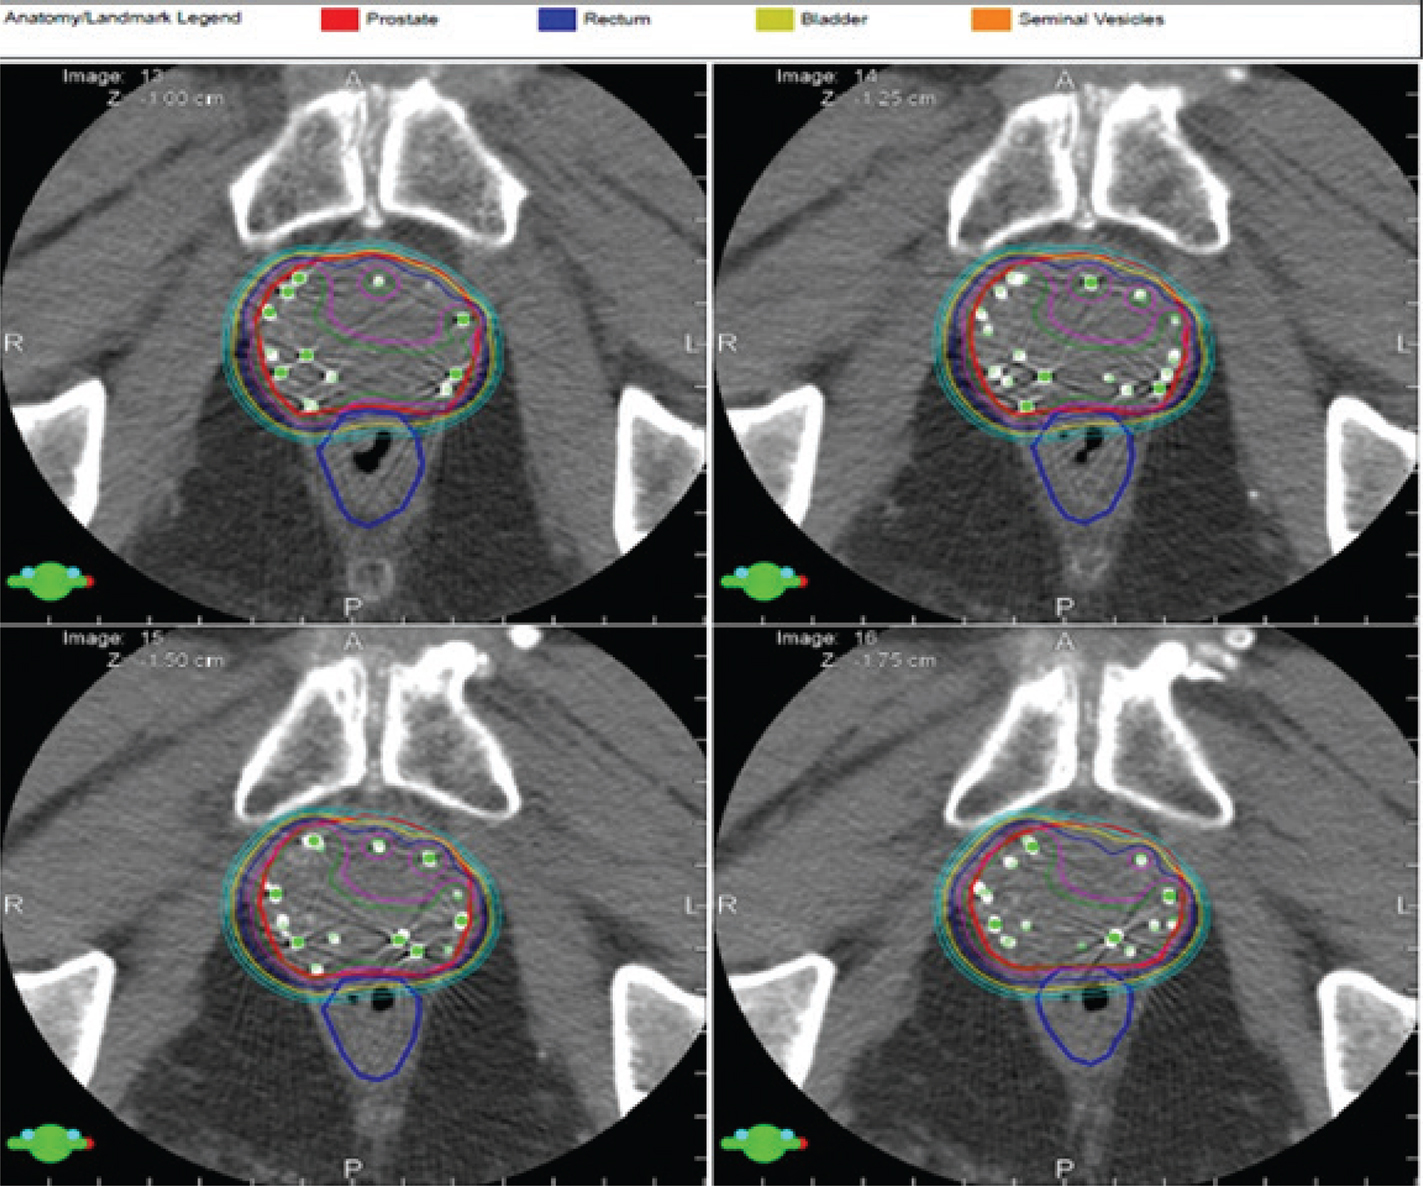

Radiation therapy after prostatectomy remains an important component of patient care. Although surgery remains an important option for patient care in prostate cancer management, often surgeons are confronted with more challenges than anticipated with extracapsular spread of tumor, lymph node involvement, perineural invasion, Gleason grade, and seminal vesicle invasion; all these are indicators of risk for local regional recurrence of disease. Although debate continues as to when to intervene with radiation therapy post-operatively, many in the radiation oncology community feel treatment is more efficacious earlier in the disease process (2326). In contrast, many in the urology community prefer to defer referral of the patient to radiation oncology until there is continuous elevation in PSA (24, 27, 28). Evidence today suggests efficacy with earlier intervention than later before PSA becomes significantly elevated. Having established this point, the radiation oncology community is challenged by defining a target to treat as treatment is being directed to a biomarker. Radiation oncologists have traditionally targeted the urethral anastomosis, former prostate capsule, and the undersurface of the bladder as high-risk targets with nodal volume therapy treated at the discretion of the radiation oncologist on an individual basis driven by the initial pathology. Although this demonstrated success, the choice of targets was thoughtful but simultaneously arbitrary based on the perception of tissues considered at risk (2931). Modern imaging has helped radiation oncologists pivot from this position and re-visit target definitions by optimizing targets that would be considered high risk and targets of intermediate risk with the option of dose painting to high-risk targets (Figure 3). In this case, metabolic imaging supported the identification of a bulk tumor aggregate which could be treated as a high-risk target with adjoining tissue, and tissue previously defined as high risk defined at intermediate risk, thus limiting the risk of normal tissue injury. The high dose volumes were titrated to areas of activity defined on anatomical imaging.

Fig 3

Figure 3. PET imaging. (left) PET scan image of recurrent disease in a post-prostatectomy patient and the radiation therapy treatment plan (right) directed to tissues considered of high risk (PET avid) and intermediate risk (28). Image courtesy of the Department of Radiation Oncology, UMass Chan Medical School and UMass Memorial Health.